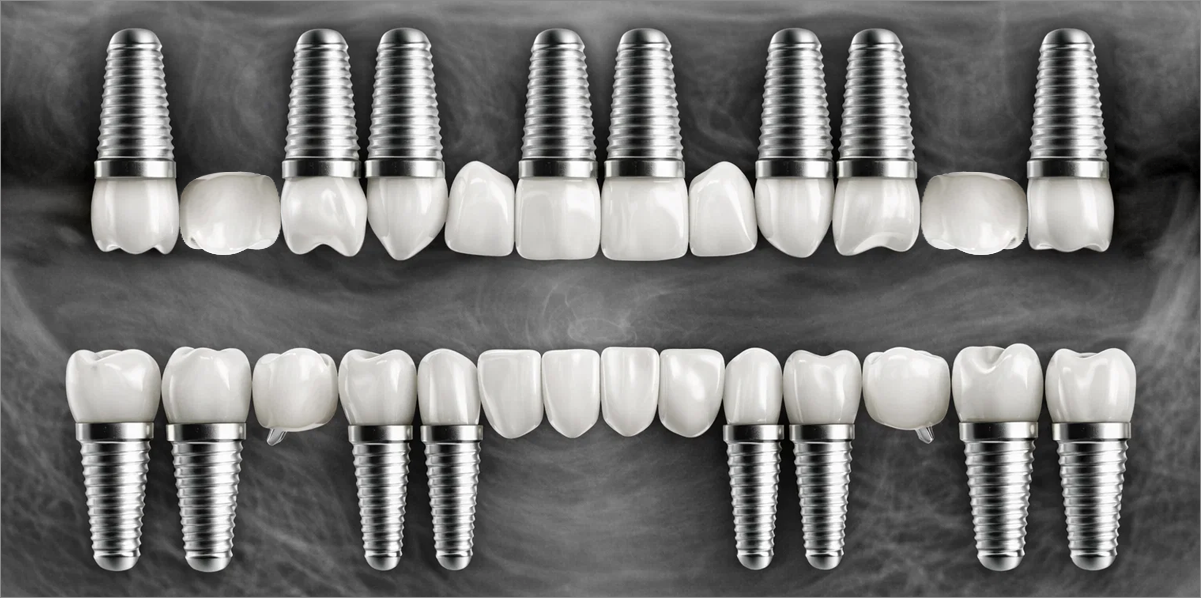

Full-mouth implant restoration is categorized into full placement or minimal placement approaches.

Full Placement

Using a method of placing 8–9 implants in the maxilla and 8 implants in the mandible, this approach fully restores all 28 natural teeth, creating an oral environment most closely resembling

natural dentition.

• 02

Minimal Placement

Using a method of placing 6–7 implants in the maxilla and 6 in the mandible, this approach restores both posterior and anterior teeth, efficiently rehabilitating the entire oral cavity.